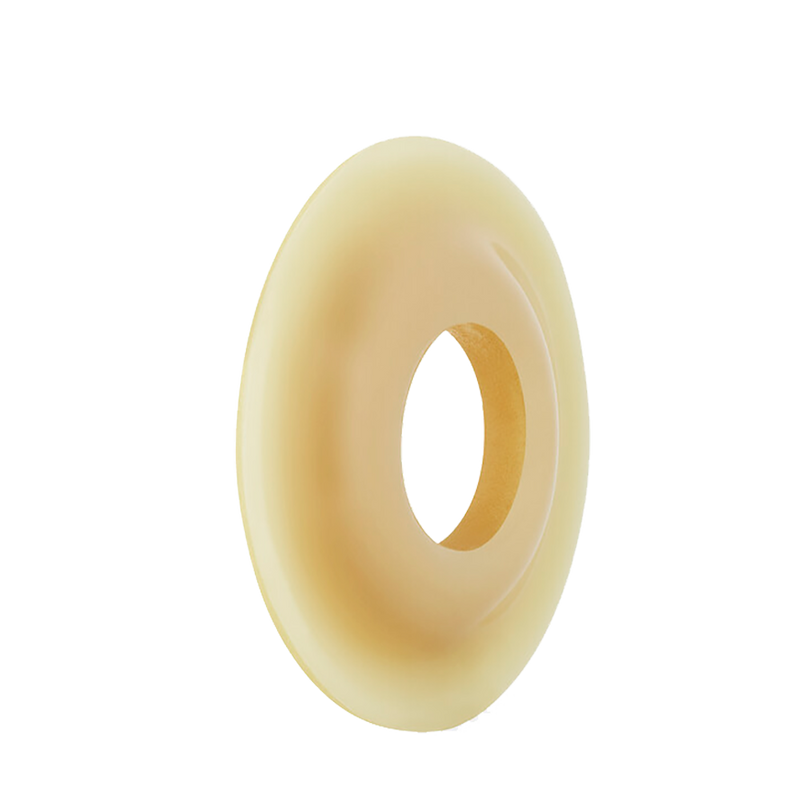

Bx/10 Brava Protective Ring Convex 35/75mm 6.6mm For Flush & Retracted Stomas. The Bx/10 Brava Protective Ring Convex (35/75mm, 6.6mm) is designed specifically for flush and retracted stomas, providing targeted support and protection. Its convex shape helps to gently contour around the stoma, ensuring a secure fit and reducing the risk of leakage. This protective ring enhances adhesion and comfort, promoting skin integrity and confidence for users managing challenging stoma profiles. Ideal for expert care, it offers reliable performance in maintaining a secure and hygienic seal.